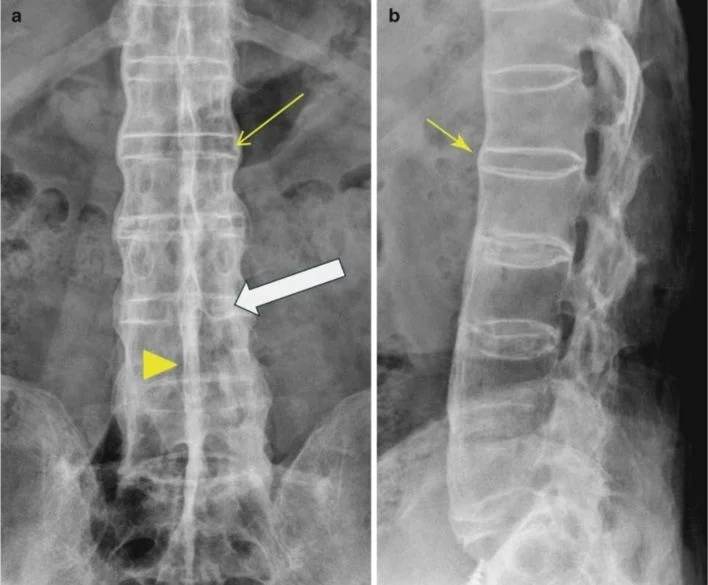

- Chẩn đoán hình ảnh: Chụp X-quang hoặc MRI có thể giúp quan sát tổn thương ở cột sống và khớp, xác định sự dính cứng của các đốt sống hoặc sự viêm ở khớp.